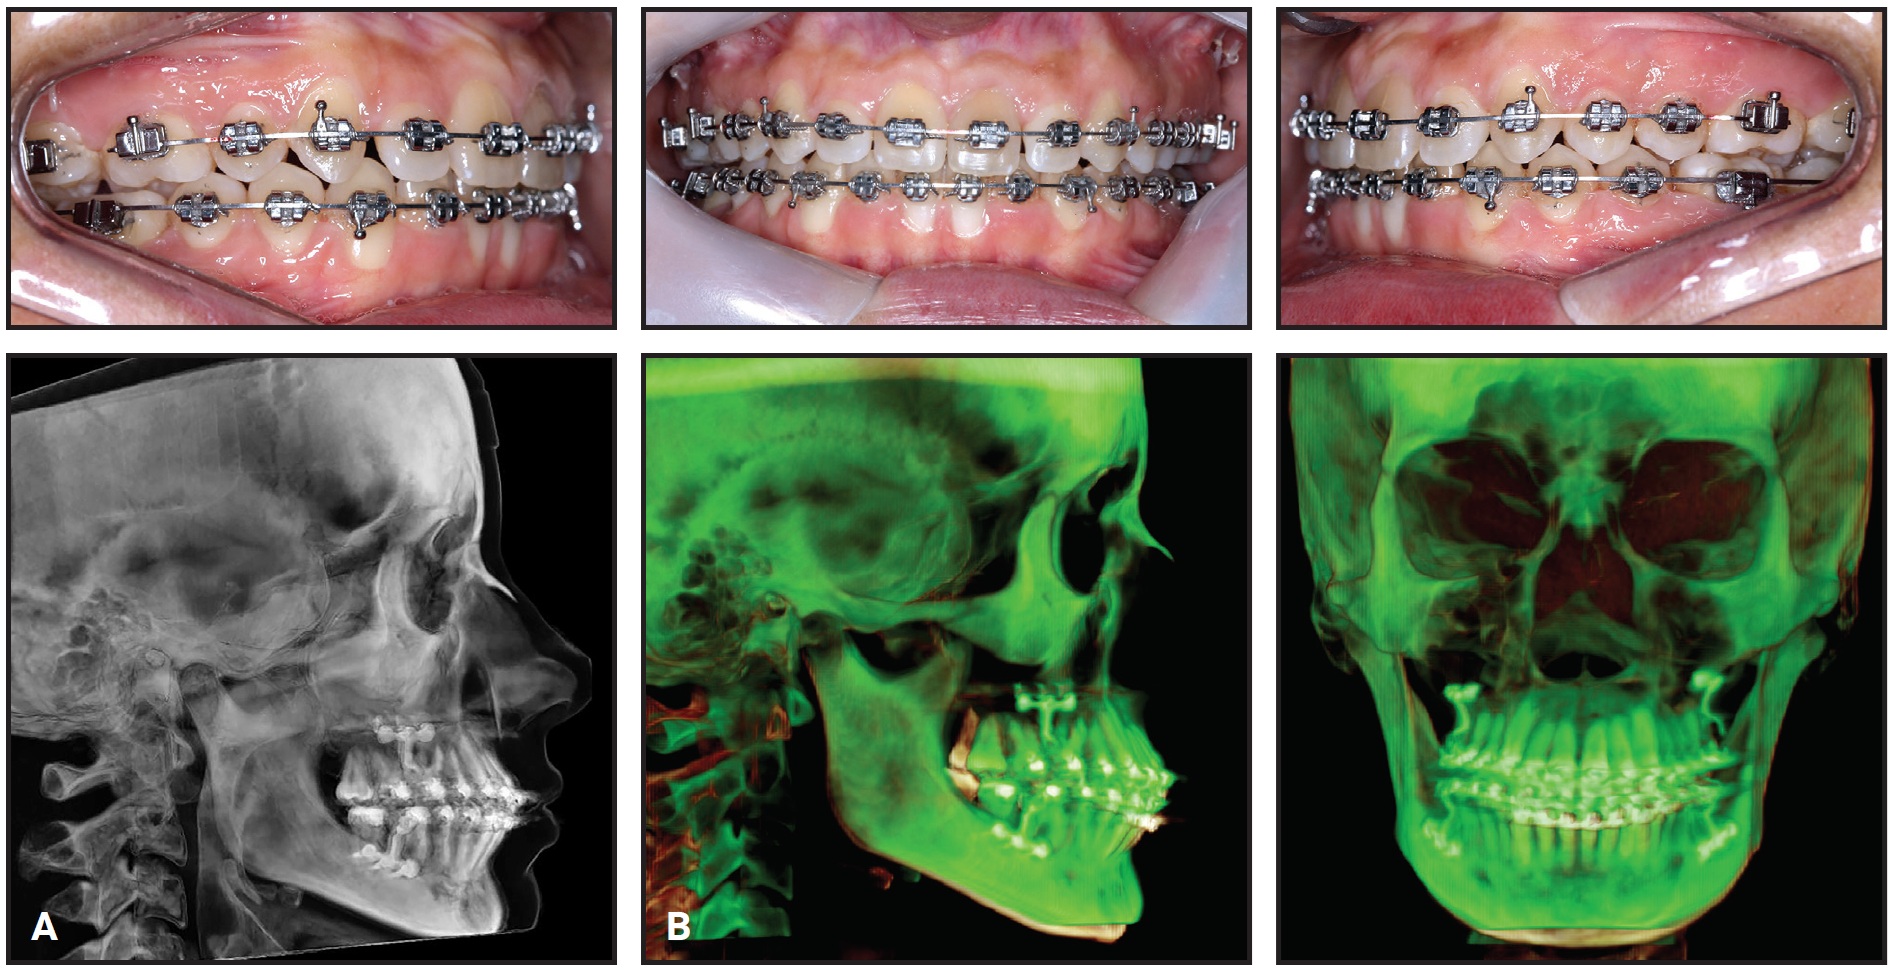

A 27-year-old female presented for removal of lower fixed appliances after about seven years of prior orthodontic treatment (Fig. 1). Her chief complaint was a lack of vertical interincisinal contact.

Fig. 1 27-year-old female patient with skeletal Class I malocclusion and anterior open bite (lower fixed appliances remaining from previous treatment).

From a frontal view, the patient had normal symmetry and zygomatic projection; the lateral assessment found a straight profile with good zygomatic projection and a normal nasolabial angle and chin-neck line. Excessive lingual inclination of the upper posterior teeth was observed in smiling, but the upper incisor display was acceptable in smiling and at rest. The patient showed an anterior open bite, with extruded and lingually inclined upper posterior teeth and intruded lower anterior teeth. The lower right first premolar was missing. Darkened upper central incisors and gingival hyperplasia on the lower lateral incisors were also noted.

Cone-beam computed tomography (CBCT) using an extended field of view and the SYM Protocol (a systematic method of diagnosis and treatment planning based on tomography) indicated overall symmetry and a skeletal Class I malocclusion associated with an anterior open bite (Fig. 2).

Fig. 2 Images created with cone-beam computed tomography (CBCT) and SYM Protocol.

A mesofacial growth pattern and good maxillomandibular positioning were observed in the three-dimensional side view. Anteroposterior and anteroinferior views confirmed facial symmetry and correspondence of the upper and lower dental midlines with the facial midline. The condyles were centered, with their cortical bones intact. A close-up view showed that upper incisors were properly positioned, but the lower incisors were tipped forward. The panoramic radiograph generated from the CBCT scan revealed mesially angulated lower teeth and a possible endodontic lesion at the apex of the lower left central incisor, which was confirmed with periapical radiographs.

The maxilla showed two distinct occlusal planes, one anterior and one posterior. This alteration of the occlusal plane was probably related to the patient’s habitual mouthbreathing during childhood and adolescence. Gravity had caused extrusion of the upper posterior teeth, which came into premature contact during closure, resulting in the anterior open bite. Because of the posterior extrusion, skeletal anchorage was considered essential to avoid premolar extractions or orthognathic surgery.